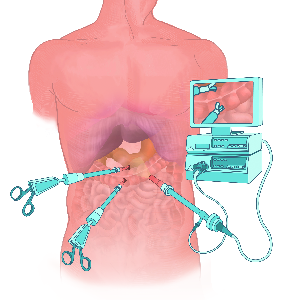

Detailreiche Fotografien aus der medizinischen Praxis ergänzen die Texte; moderne, genaue,

wissenschaftliche Zeichnungen geben Einblick in die Anatomie und die Funktion der Lunge und

anderer Organe.